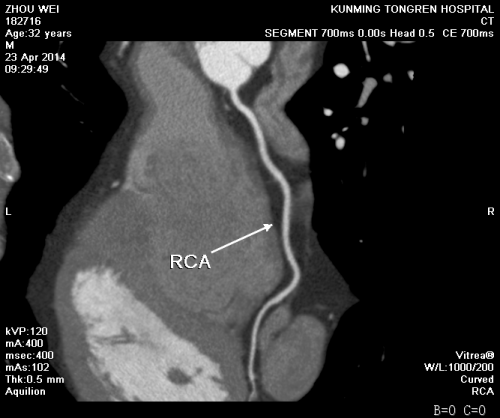

我院影像科冠状动脉CT造影片如下图: